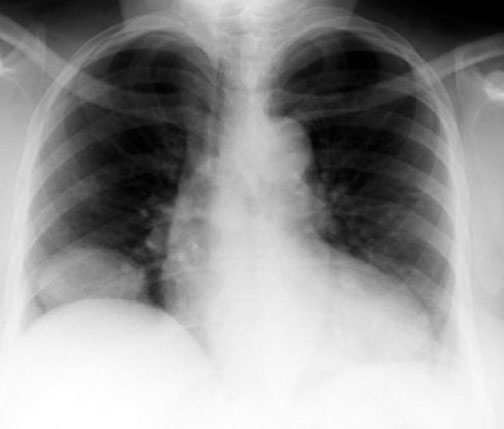

Eventration / Localized

• Herniation of Liver